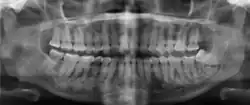

| Florid osseous dysplasia of the mandible | |

| Diagnostic method | X-ray, CBCT scan, vitality testing of teeth |

Cemento-osseous dysplasia (COD) is a benign condition of the jaws that may arise from the fibroblasts of the periodontal ligaments. It is most common in middle-aged females of African descent. The three types are periapical cemental dysplasia (common in those of African descent), focal cemento-osseous dysplasia (Caucasians), and florid cemento-osseous dysplasia (African descent). Periapical COD occurs most commonly in the mandibular anterior teeth while focal COD appears predominantly in the mandibular posterior teeth. Florid COD is an extensive variant of periapical COD where lesions occur in multiple quadrants which can encompass the maxilla and mandible, and infrequently can cause jawbone deformity.[1]

Diagnosis is based on clinical and radiographic observations, and in rare cases, biopsy may be performed.[3] Diagnosis is important so that the treating doctor does not confuse it for another periapical disease such as rarefying osteitis or condensing osteitis. Incorrect diagnosis could lead to unnecessary root canal treatments, or biopsy or surgical intervention which can be invasive and increase the risk of infection.[5] A pulp vitality test such as a cold test or electric pulp test can aid in diagnosis, since COD generally does not compromise pulp vitality.[6] COD can be found in individuals of all ages and ethnic backgrounds, but it has been observed more frequently in individuals of African, East Asian, and Asian descent.[7] Cone-beam computed tomography (CBCT) has proven useful in distinguishing between COD and periapical cysts, when examined with quantitative texture analysis using specialized software.[5]